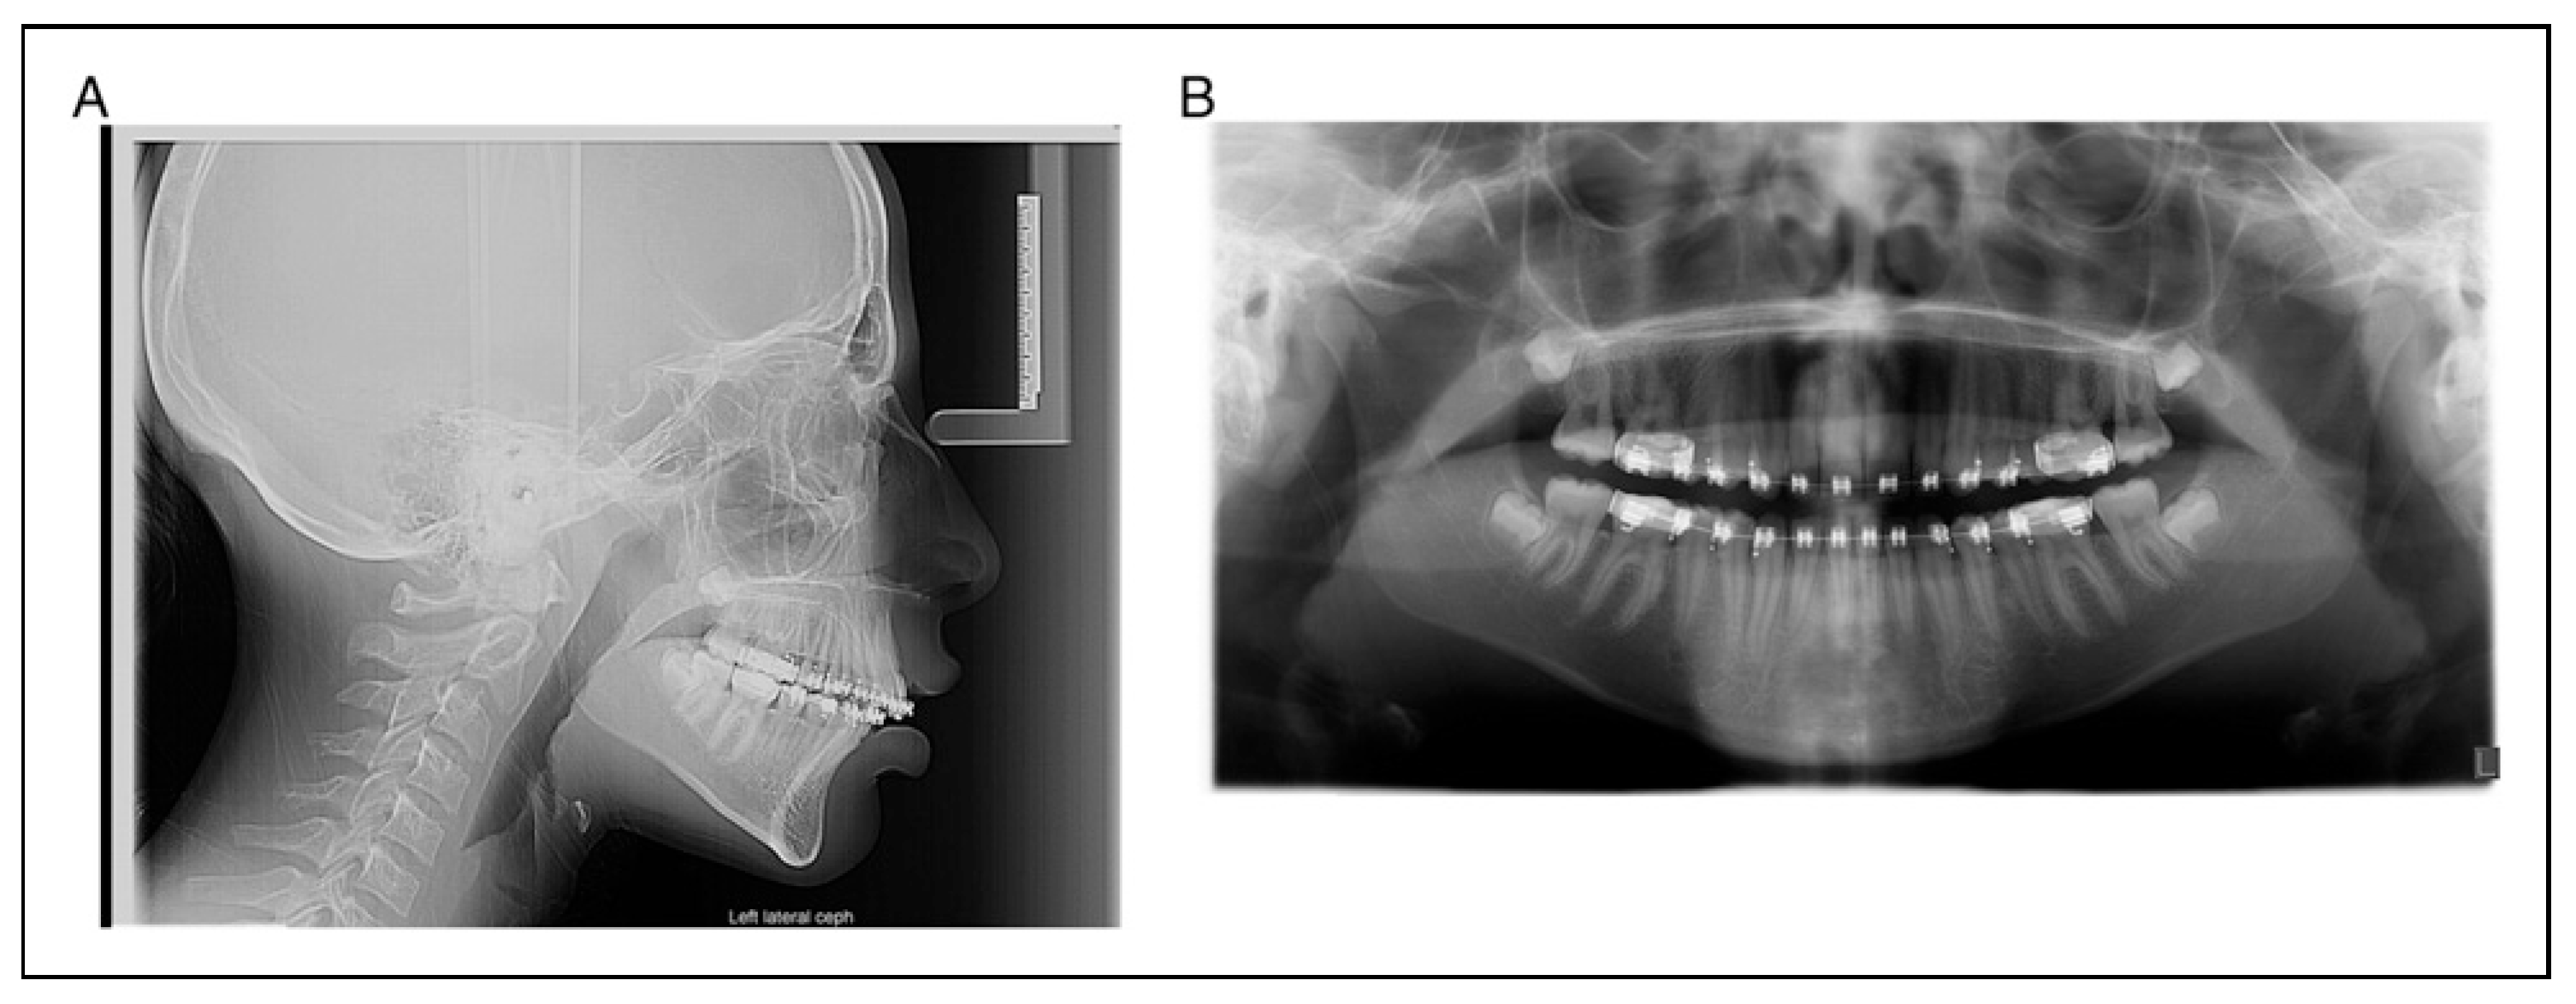

A 17-year-old woman presented for evaluation and treatment of mandibular hypoplasia (Figure 1A and 1B). Her medical history was significant for type I diabetes mellitus with an A1C of 8.1 one week prior to surgery. Her only prior surgery was tonsillectomy as a young child from which she recovered without issue. Her social history of negative for tobacco, alcohol, and drug use (smoking, vaping, use of tobacco of any kind). She received 1 g of cefazolin prior to incision. A bilateral sagittal split osteotomy (BSSO) was performed without intraoperative complication. Her lower third molars were not visualized during the surgery and were left in place. It was felt that removing them would lead to an unplanned fracture of the distal segment and that they would be removed at a later date. The mandible was fixed with a single 4-hole mono-cortical miniplate as well as 1 posterior bicortical screw bilaterally (Figure 2A and 2B). Her postoperative course was benign. She was admitted for 23-h observation during which time she received 2 doses of 3 g of Unasyn. She tolerated a clear liquid diet; postoperative radiographs were obtained (Figure 2A and 2B).

Figure 2. A, B postoperative cephalometric and panoramic images one month after surgery.